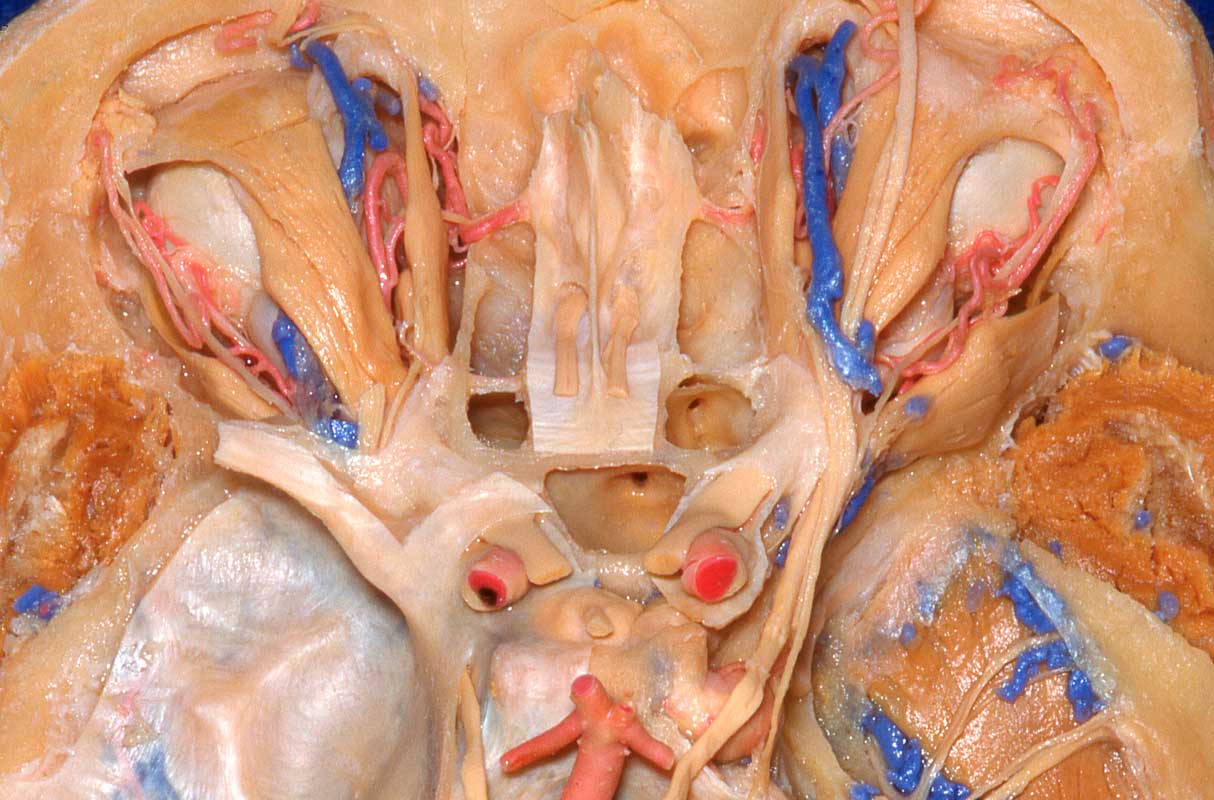

Tratamento cirúrgico de radionecrose cerebral, complicação de radiocirurgia estereotáxica em meningiomas de base de crânio

Este é o relato de um caso de uma paciente que foi encaminhada para nossa equipe após ter desenvolvido radionecrose cerebral devido a radiocirurgia para tratar pequeno meningioma da base do crânio. Removemos o tumor e o tecido necrosado sem intercorrências.